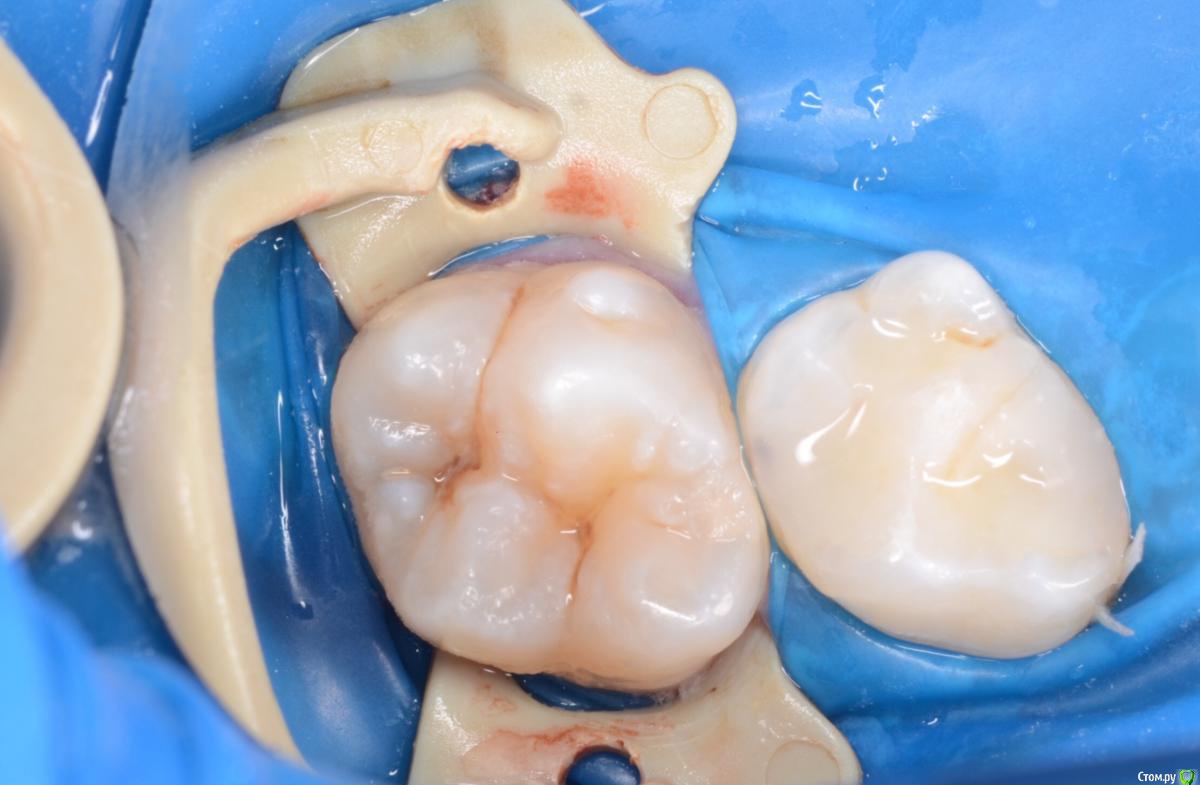

CRAZYDUCK Опубликовано 3 мая, 2018 Поделиться Опубликовано 3 мая, 2018 Обратимый пульпит 4.6 ,почти 8 лет ( в середине мая )сначала сделала силиконовый ключ .1.препарирование 2.вскрытый рог - кровотечение незначительное 3.спонтанный гемостаз (через 4-5 минут после вскрытия )4. ХГ 2% 5. МТА ( рутдент быстротвердеющий технодент ) застывает за 8-10 минут 6. Calcimol изолирующая, убираю излишки , Rondoflex 7. Реставрация с помощью силиконового ключа.8. Полировка .Наблюдаем - осмотр реставрации , витальность и RVG каждые 3-4 месяца. 6 Ссылка на комментарий